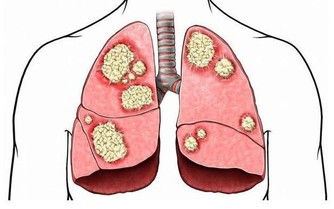

*****1.清肺護肺早點戒掉煙*****

在男性吸煙者中,一生肺癌發病風險為17.2%。而不吸煙者的風險僅為1.3%。

對吸煙者來說,清除肺部有害物質,首先要做的肯定是戒菸!

多吃西藍花、芥藍、甘藍等十字花科的蔬菜,有助清除肺部有害細菌。

中醫以白色食物來清肺防燥,平日容易感冒,或是肺與支氣管常不舒服、易咳嗽的人要多吃一些白色的食物,

例如白蘿蔔、白菜、甘蔗等蔬菜,杏仁、山藥、百合和白芍等。